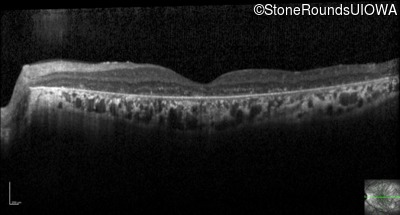

Optical Coherence Tomography - Right - 20/40 -1

Exemplar / OCT Stack

OCT Stack